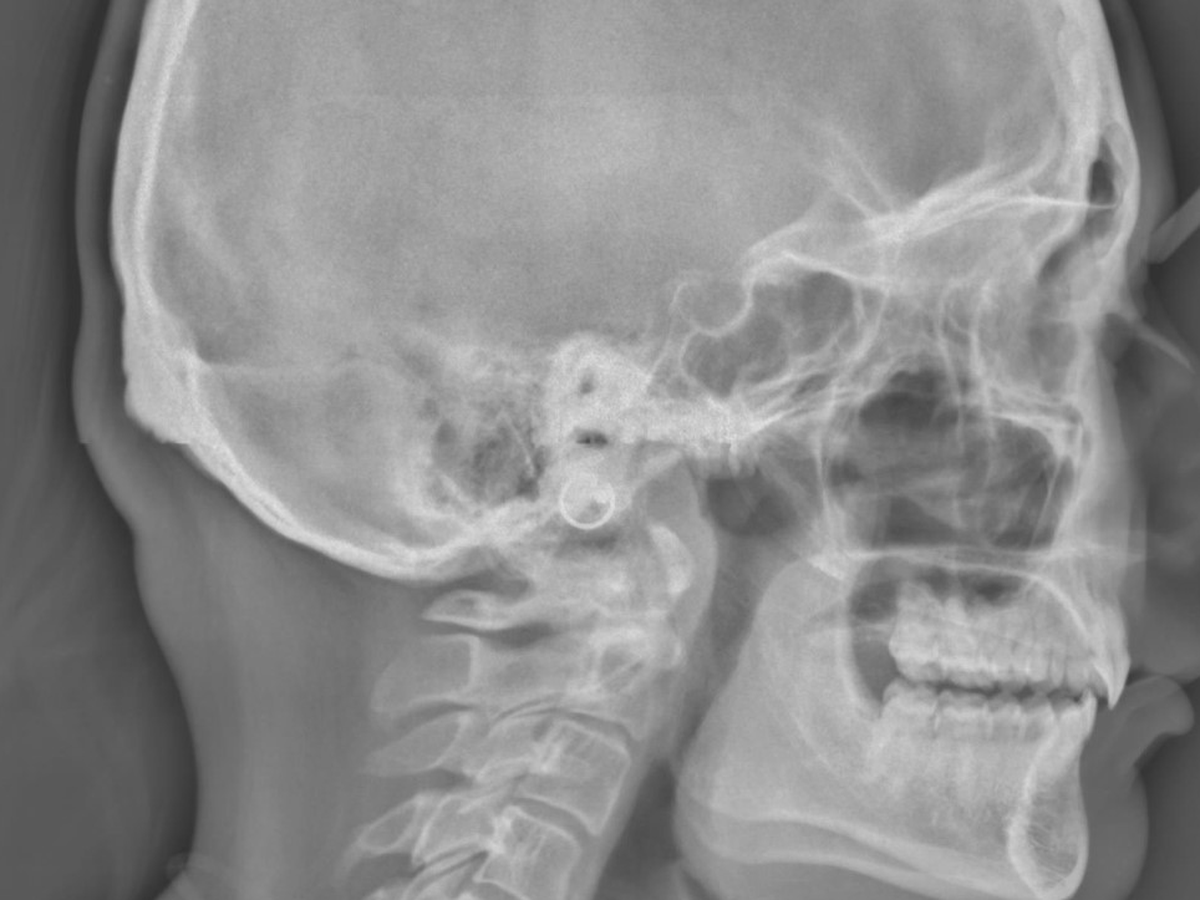

Due to her Turner Syndrome her jaw is recessed very badly. You can see it in the xray I have attached. This jaw recession in effect, restricts her airway at night which is causing her exhaustion.